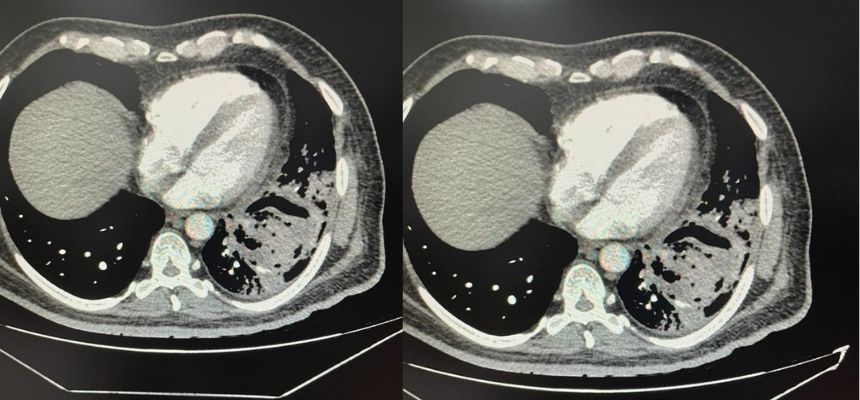

The patient, Mr. Rama Nageshwar Rao, was rushed to SLG Hospitals on 10th July, after he started coughing blood due to severe cough. CT scan revealed acute damage caused to the lower lobe of the left lung, along with a deep cavity in it. A presumptive diagnosis of the condition was the post-Covid lung damage or cavity in the lung due to past Covid-19 infection caused in the month of May this year.

Commenting on the condition and treatment administered, Dr. Vivek Babu Bojjawar, Consultant Cardiothoracic & Vascular Surgeon, SLG Hospitals said, “Aspergilloma is normally noticed among people with weak immune system. While this is commonly found among patients suffering with tuberculosis, finding it as an after-affect of Covid-19 infection is a first! This condition damages lungs, causes cavity, and could result in fatality at an advanced stage. Vomiting blood by Mr. Rao is an indication the spread of this virus is deep and necessitated an emergency surgery.”

“A lobectomy surgery was performed on the patient to remove the virus ball along with traces of damaged lung. This condition can be seen as medium to long term side-effect of Covid-19 infection, and such conditions must be traced and treated early before they develop into health emergencies necessitating surgical procedures,” added Dr. Vivek Babu.